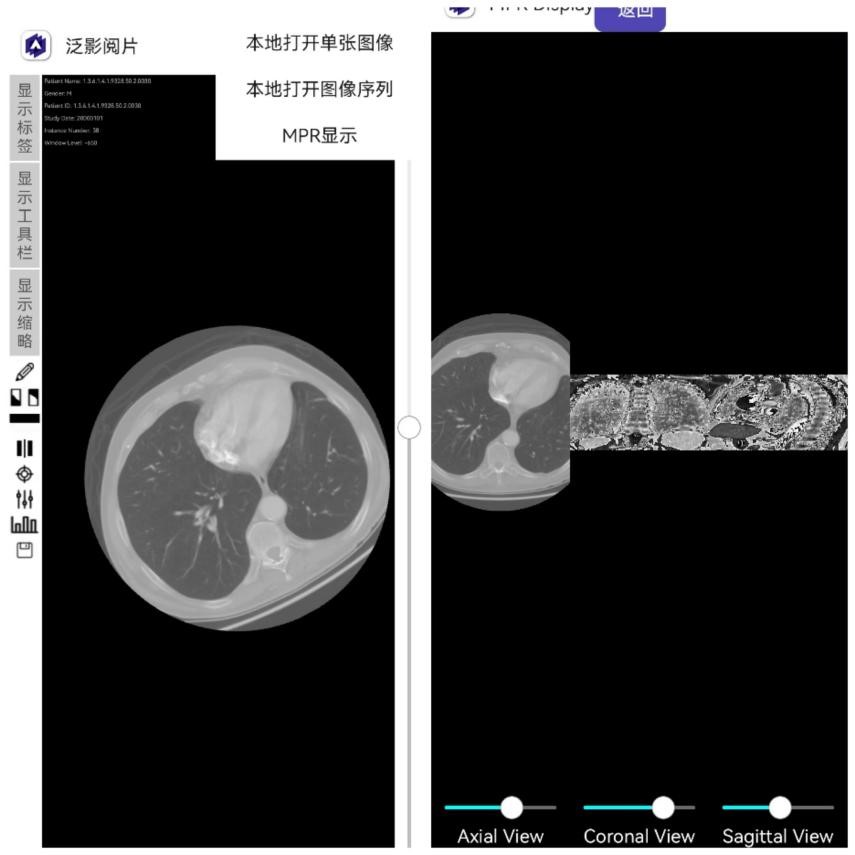

打开序列后,可以选择MPR(多平面重构)显示功能。在MPR页面会将原始的轴状面图像序列进行三维重构,拖动冠状面及矢状面的滑动条可以分别针对这两个维度在不同位置上进行切面,以形成重构出的对应图像,如下图所示。